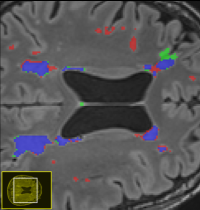

Interdisciplinary Bachelor thesis in the domain of "Automated Segmentation of WMH"

White matter hyperintensities (WMHs) are among the signs of vascular dementia on conventional MRI. In this thesis, relevant automated algorithms for segmentation of WMHs shall be compared for their performance on a clinical cohort.